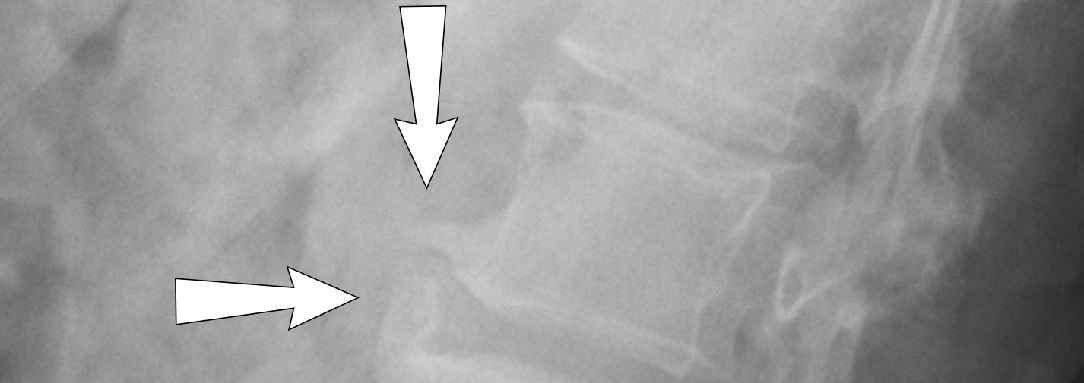

LUMBÁLNÍ SPONDYLÓZA

Příčiny bederní spondylózy se v zásadě od krční podstatně neliší.

Rovněž u lumbální spondylózy je nejúčinnějším prostředkem dynamická lordotická trakce.